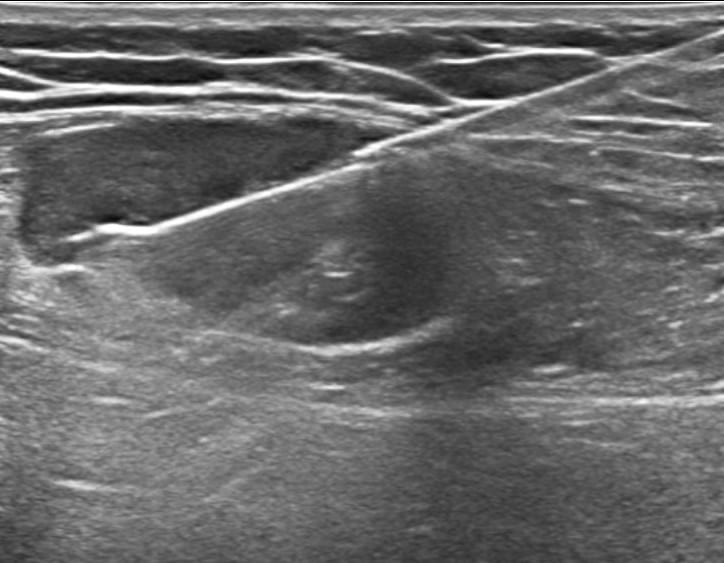

- Υπερηχογράφημα επιφανειακών λεμφαδένων: εξηγεί μορφολογία και αγγείωση. Π.χ. ωοειδές σχήμα με λιπώδη πύλη τείνει να είναι καλοήθες, ενώ στρογγυλοποίηση (λόγος μήκους/πάχους <2), απώλεια πύλης, ανομοιογένεια, νεκρώσεις ή περιφερική αγγείωση αυξάνουν την υποψία κακοήθειας.